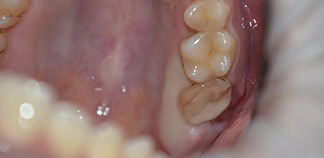

Как лечили

Удален сколотый седьмой зуб. Проведена аутотрансплантация восьмого зуба в подготовленную лунку. Через три месяца жалоб от пациента не поступило.